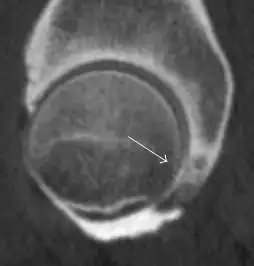

Most of the angles and measurements described in the plain radiograph section can be accurately reproduced on MRI. In addition, the superiority of MRI resolution with intra-articular contrast allows detection of labral and chondral abnormalities that may influence the choice of medical, percutaneous, or surgical management (Figure 9).[1]

Figure 9:

Sagittal T1 weighted image showing chondral lesion.[1] -

Association between labral tears and chondral damage has been demonstrated. This underscores the interaction between cartilage and labrum damage in the progression of osteoarthritis. Chondral damage to the posteroinferior part of the acetabulum as a contrecoup lesion occurs in approximately one-third of pincer cases secondary to persistent abutment on the anterior part of the joint leading to a slight posteroinferior subluxation. This is considered a bad prognosis sign.[1]